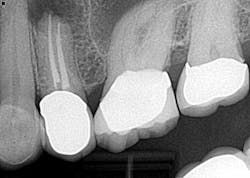

Case report A healthy 61-year-old female presents with a chief complaint of pain and discomfort in the upper left quadrant. A radiograph revealed a large radiolucency at the apex of tooth No. 12. An irregular root apex was also noted. Clinically No. 12 was sensitive to percussion and palpation in the buccal vestibular area. There was no response to cold. Diagnosis was necrotic tooth No. 12 with associated periapical abscess. RCT was recommended and the patient was referred to a specialist for completion. RCT was completed — no complications were noted and the prognosis was given as good. (Figs. 1 and 2) The patient was placed on recall by the endodontist for reevaluation of the lesion in 12 months.Fig 1. Fig. 2Eight months later, the patient presented back to the office stating that she felt pressure again in the upper left area. A radiograph of No. 12 showed an increased radiolucency around the apex of tooth No. 12. Furthermore, there was a draining fistula in the buccal vestibule. Diagnosis was persistent infection/disease, likely due to the initial presentation and presence of the cyst. (Fig. 3)

Fig. 3The patient did not want to lose her tooth and was referred back to the specialist for an evaluation and consideration of options. It was discussed and recommended that the patient have root end resection with a root end filling (apicoectomy). She agreed, and the treatment was completed. There was suspicion as to the nature of the pathology of the cyst-like lesion, so it was sent out for biopsy. Diagnosis was chronic, localized osteitis and actinomyces colony. Conclusively, the source of the infection was eradicated but the presence of the actinomyces microorganism was enough to sustain a chronic infection post-initial RCT. (Fig. 4)